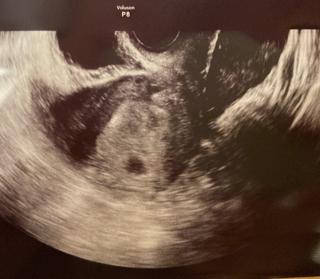

過去に2回流産しており、不安な妊婦生活を送っていますが、無事に12.2mmの胎嚢を確認することができました!写真だと分かりづらいけど、卵黄囊も見えました。過去2回の妊娠と比べても、いちばん順調な大きさ。先生のリアクション的にも順調なのかな!今度こそ産んであげたいです。